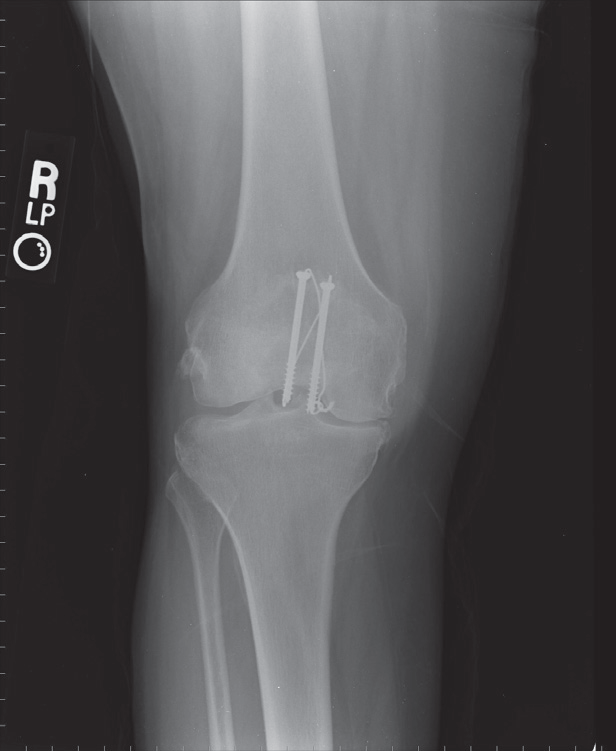

Dislocerede frakturer

Indlægges til åben osteosyntese.

Billedresultat for patella fracture x-ray

Operationen behøver ikke nødvendigvis ske i vagten, medmindre det drejer sig om en åben fraktur.

Postoperativ rtg kontrol.

Må mobiliseres med hængselbandage 0-30 grader 14 dage med krykker og støtte på strakt knæ. Amb kontrol i fys med suturfjernelse og oplåsning 0-60 uge 2-4 og 0-90 uge 4-6. Amb kontorl6 uger med rtg kontrol og bandage fjernelse.